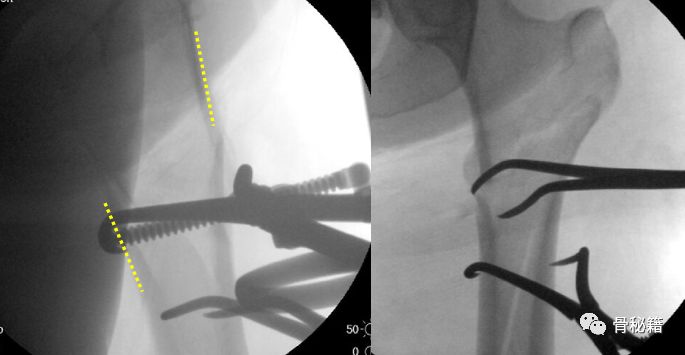

2.将该导针套上一个套筒直达骨皮质,套筒上夹kocher钳,远端连接T把手

3.下面就是复位了,将带螺纹的导针经过T把手向外侧拉,同时向内侧推kocher钳和所夹的套筒。这样一个进一个出,就完成了复位。

4.这种情况下就可以在复位加压的情况下完成骨折的扩髓和固定了